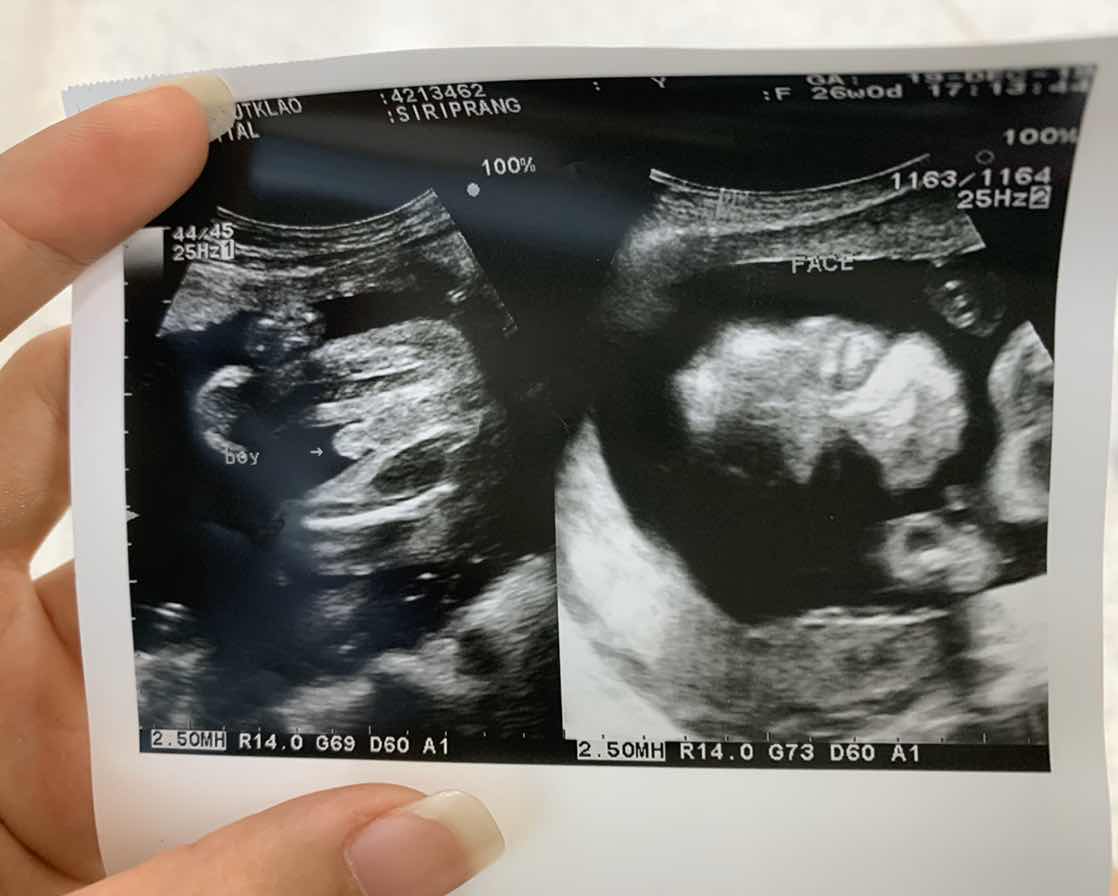

บ้านนี้ได้จู๋จ้า

บ้านนี้ผู้ชายค่ะ

บ้านนี้มีแท่งจ้า